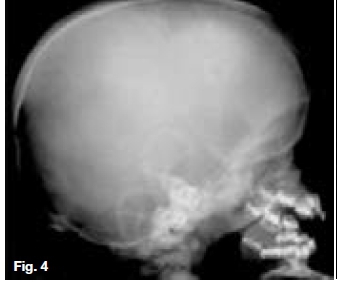

Below are cases of two very rare genetic disorders. Figures 1, 2 & 3 are of an inherited form of dwarfism associated with fragile bones, while Figures 4, 5, & 6 are cases of metabolic disturbances affecting the skull, jaws and teeth. Describe the important radiological features discernible and what are your diagnoses?

Postero-anterior skull (Fig. 1) and lateral skull radiographs (Fig. 2) showing open anterior fontanelle, dense bones and small maxillary sinuses. In addition, Figure 2 also demonstrates obtuse mandibular angles. The hand-wrist radiograph (Fig. 3) shows incomplete terminal phalanges (red arrows). A diagnosis of Pyknodysostosis was made which is a genetic lysosomal disease characterized by short stature, increased density of the bones, and brittle bones. Other features may include underdevelopment of the tips of the Angers with absent or small nails, an abnormal collarbone (clavicle), distinctive facial features including a large head with a small face and chin, underdeveloped facial bones, a high forehead, and dental abnormalities. These patients are predisposed to osteomyelitis. The diagnosis of Pyknodysostosis is based on physical features and X-ray findings. Figure 4 is a lateral skull radiograph of a patient presenting with bulging of the frontal region of the skull and showing attenuation of the outlines of the dental crypts which is suggestive of a child with vitamin D deficiency. This deficiency results in rickets in childhood and is one of the causes of osteomalacia in adults. Vitamin D acts to increase intestinal calcium uptake, bone calcium mobilization reabsorption.